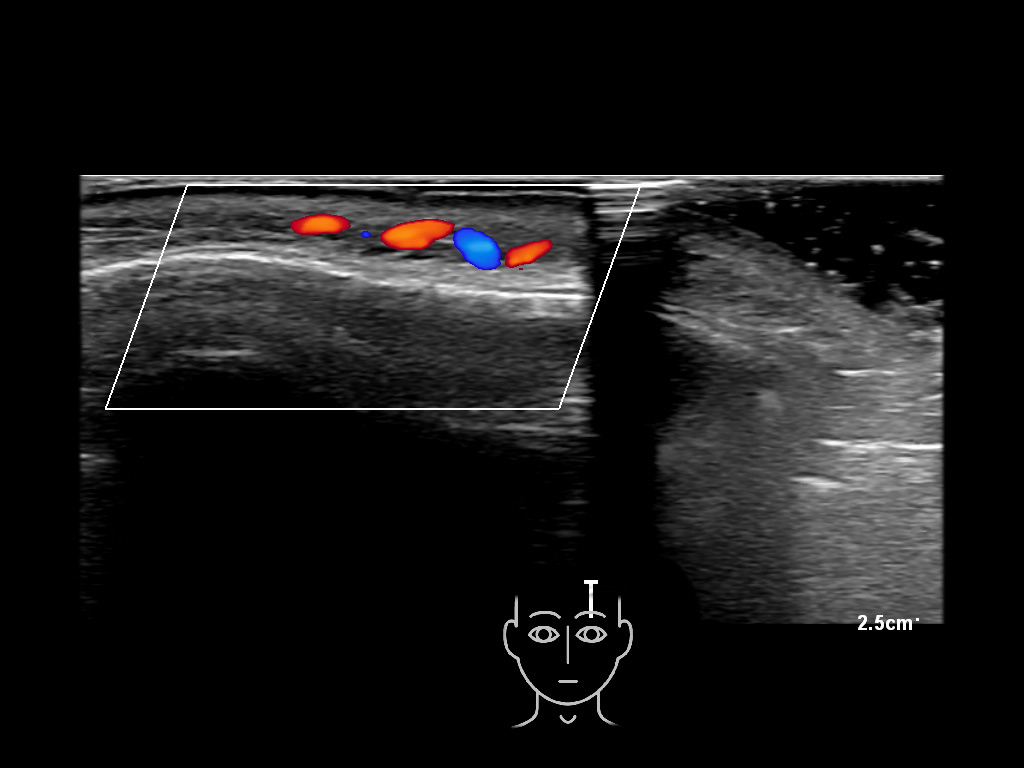

In this section you will learn more about the different layers of the face with the use of ultrasound. When you click on the secondary ultrasound image, you will see the different structures as an overlay. This will help to train yourself to recognize the different layers of the face.

Study the first image to recognize the different layers. If you are sure about the layers, swipe to the second image to view the answer (if applicable).